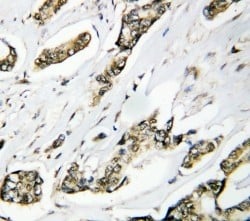

IHC (Immunohiostchemistry)

(Anti-Hsp105 antibody, AAA45180, IHC(P)IHC(P): Human Mammary Cancer Tissue)